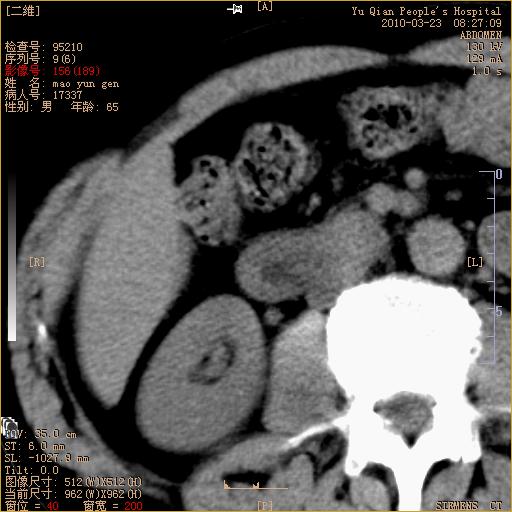

标题: CT25266:消瘦月余,前来肝部检查,请看看肠腔 [打印本页]

标题: CT25266:消瘦月余,前来肝部检查,请看看肠腔

肝区结肠占位,腺癌可考虑,建议肠镜活检。

升结肠肠壁增厚,不均强化,考虑升结肠腺癌可能性,建议肠镜检查。

1)考虑升结肠癌。2)右肾小囊肿。